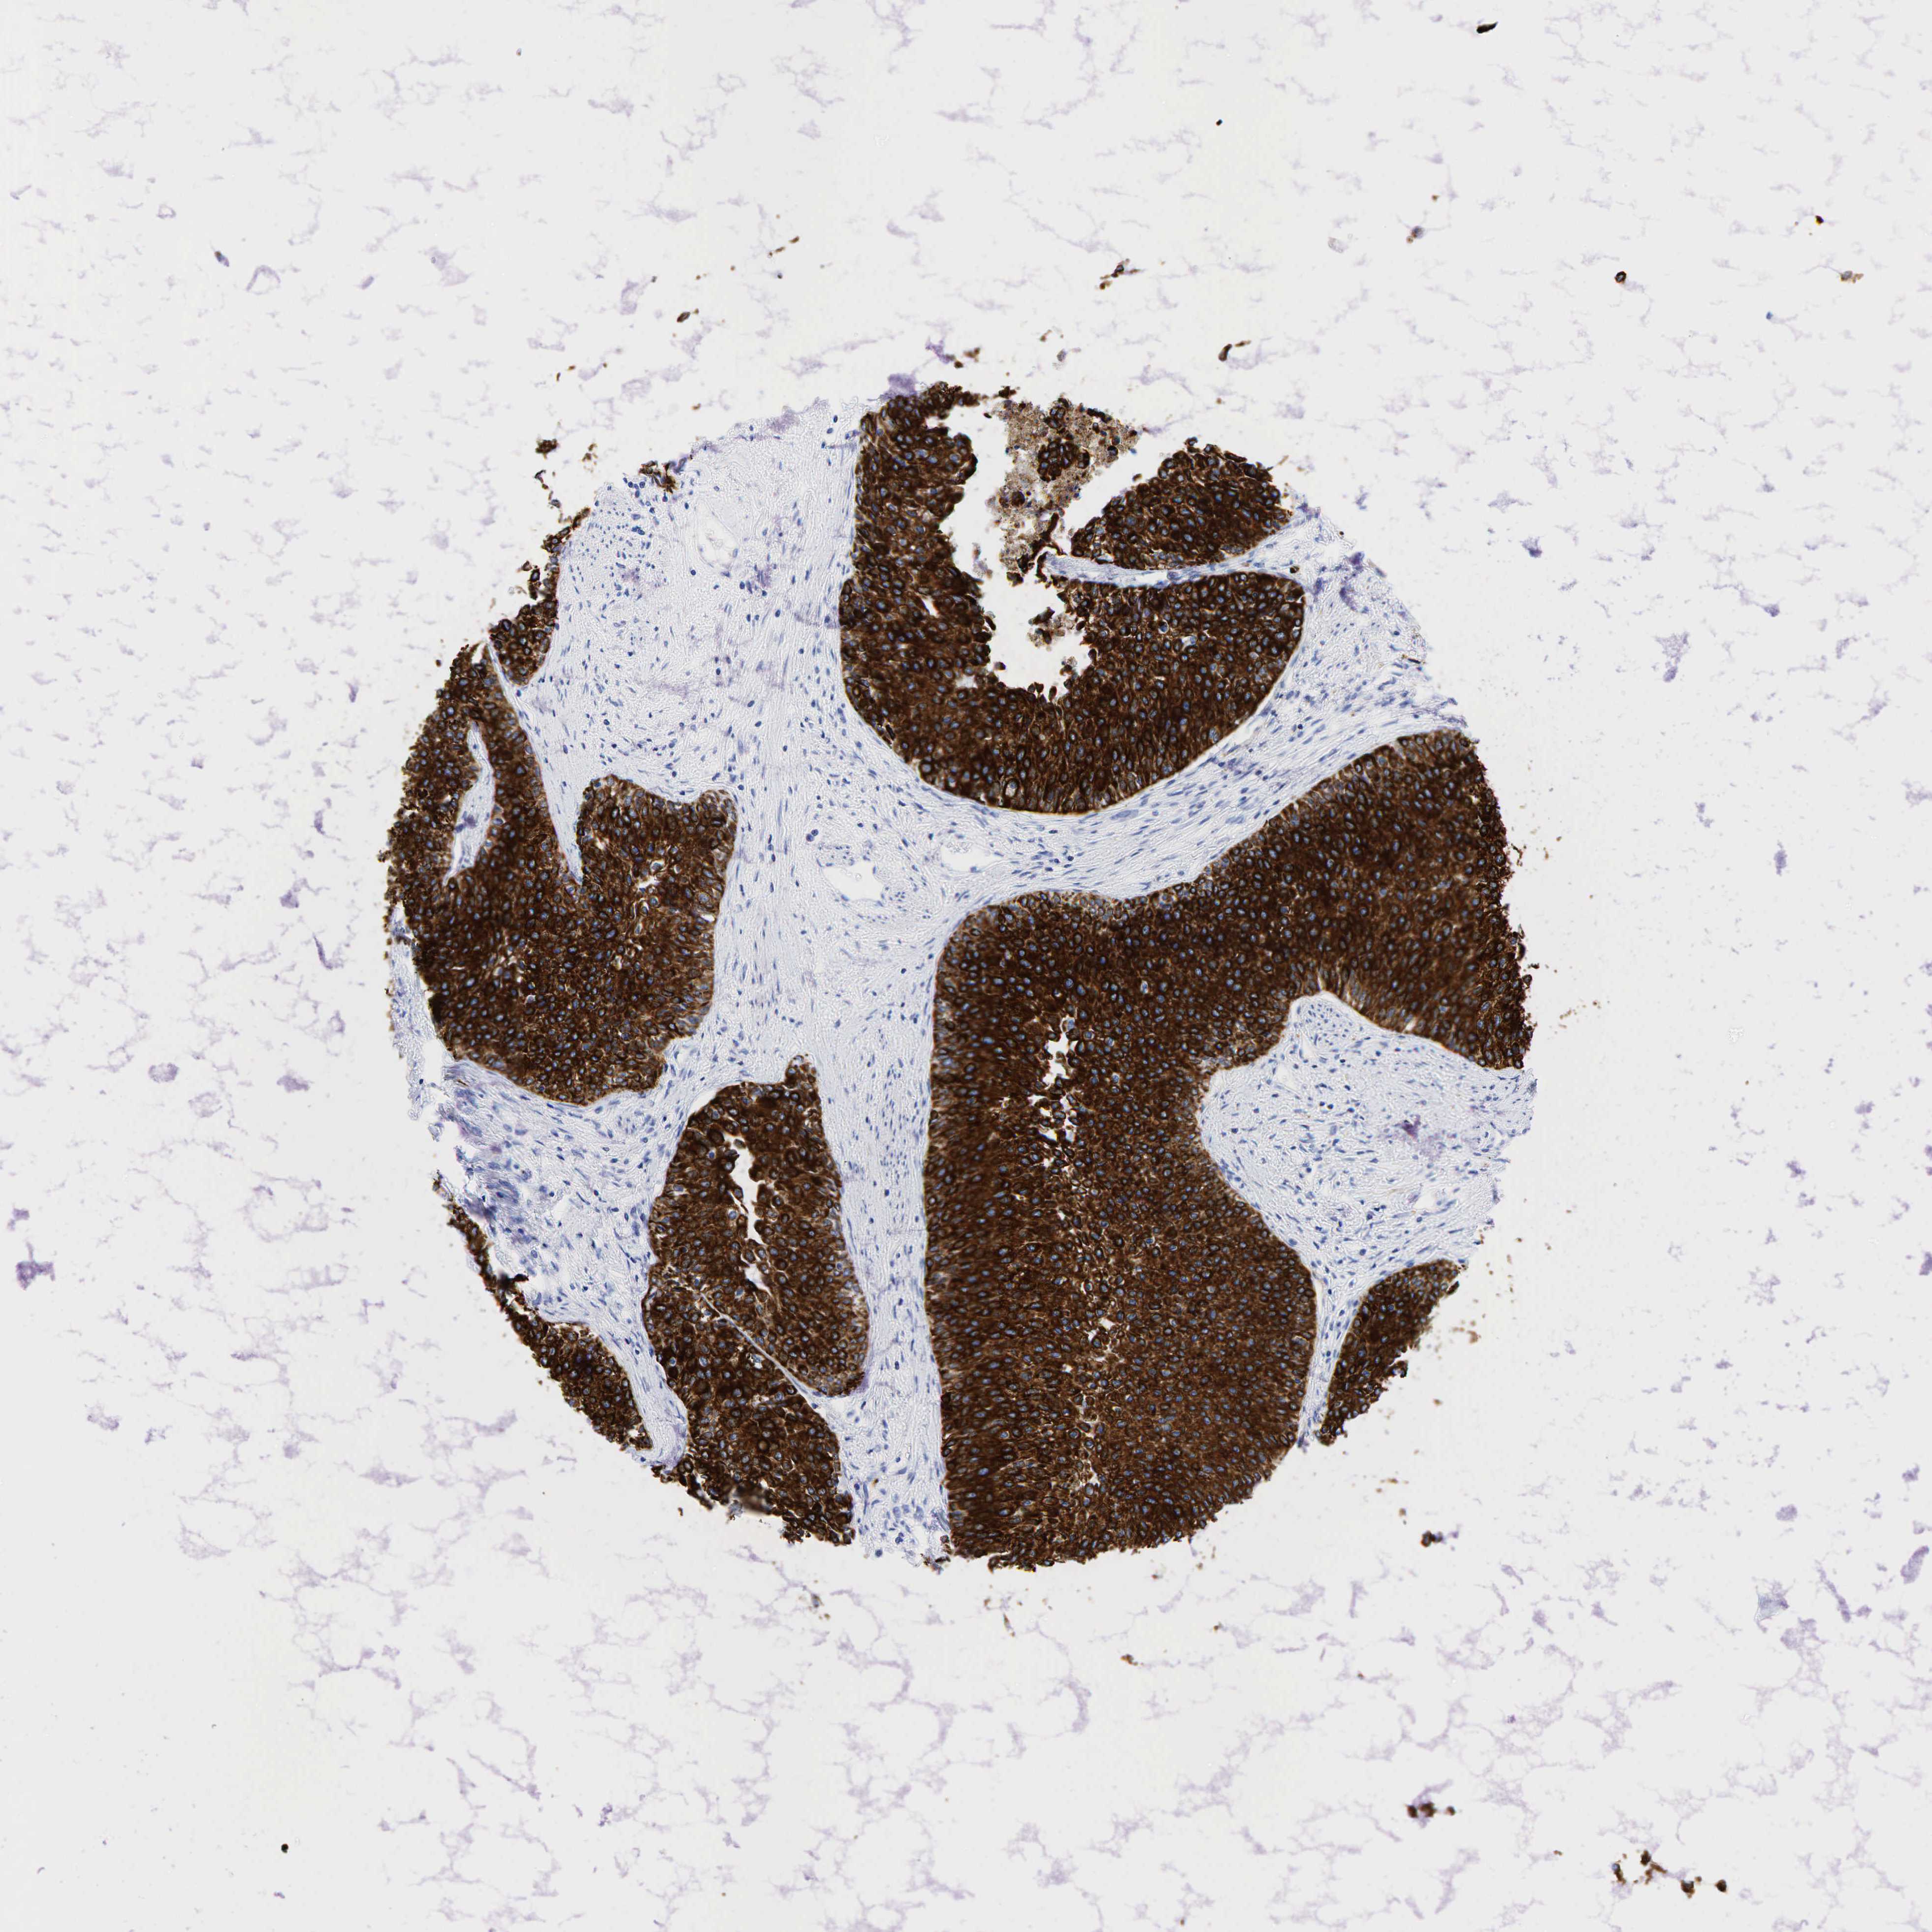

UROTHELIAL CANCER - Protein expressioni

A mouse-over function shows sample information and annotation data. Click on an image to view it in a full screen mode. Samples can be filtered based on level of antibody staining by selecting one or several of the following categories: high, medium, low and not detected. The assay and annotation is described here.

Note that samples used for immunohistochemistry by the Human Protein Atlas do not correspond to samples in the TCGA dataset.

Antibody stainingi

Antibody staining in the annotated cell types in the current human tissue is reported as not detected, low, medium, or high, based on conventional immunohistochemistry profiling in selected tissues. This score is based on the combination of the staining intensity and fraction of stained cells.

Each image is clickable and will lead to virtual microscopy that enables deeper exploration of all samples and also displays staining intensity scores, fraction scores and subcellular localization as well as patient and tissue information for each sample.

Antibody HPA002465

Antibody CAB000031

Urothelial carcinoma, High grade

Urothelial carcinoma, Low grade

Adenocarcinoma, NOS